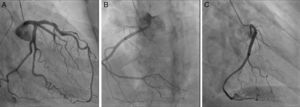

Angiografia coronária; painel A (incidência OAD30°; caud20.°) demonstrando a coronária esquerda sem lesões epicárdicas; painéis B (incidência OAE20°; cran20°) e C (OAD30°) demonstrando a coronária direita sem lesões epicárdicas e com origem na parede ântero-lateral esquerda da aorta, acima dos seios coronários.